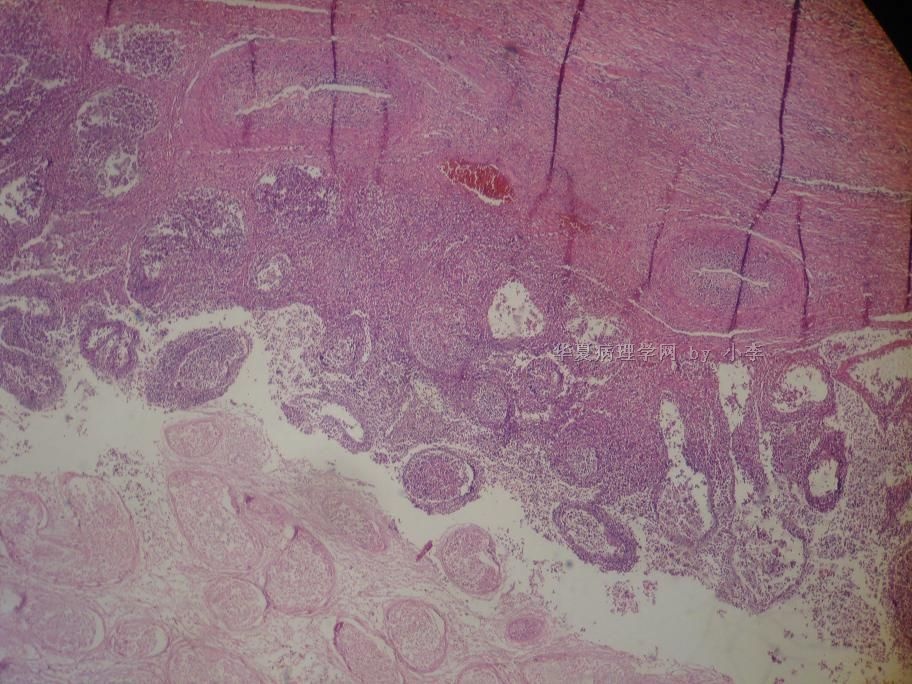

睾丸炎?

• 睾丸炎?图4

图4

首先考虑精子肉芽肿

慢性肉芽肿性炎

肉芽肿性睾丸炎

精子肉芽肿